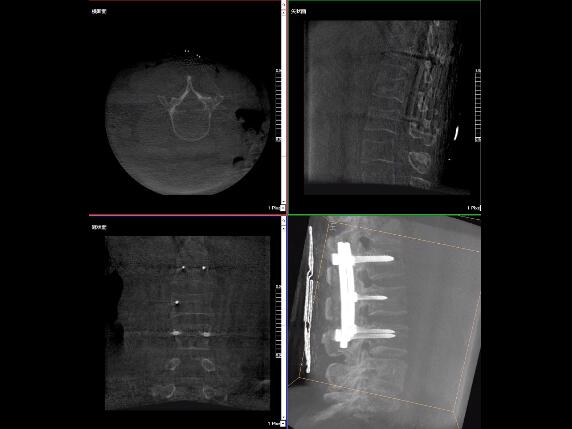

比如,醫(yī)生在做PKP(椎體成形術(shù))的時(shí)候,或者在置入螺釘?shù)臅r(shí)候,醫(yī)生需要在影像上看到螺釘打進(jìn)去的進(jìn)針點(diǎn)以及進(jìn)針的路徑。比如,我們?cè)诖蜓档尼斪訒r(shí)需要看到“貓眼”。我們只有把釘子完全打在“貓眼”里面,才能確保釘子打在了椎弓根里,所以對(duì)“貓眼”的顯影就非常重要。

“貓眼”指的是椎弓根在正位的投影。

最后我要強(qiáng)調(diào)一點(diǎn),以上我提到的“貓眼”,在二維的X光片上,醫(yī)生是靠經(jīng)驗(yàn)去判斷釘子是否打在椎弓根里,這個(gè)時(shí)候如果我們的設(shè)備再先進(jìn)一點(diǎn),診斷手段再多一點(diǎn),如果我們能夠把二維的影像轉(zhuǎn)換為三維的影像,可能就不會(huì)完全依賴醫(yī)生的經(jīng)驗(yàn)。

我們可以在三維的圖像中直觀的看到釘子到底在不在椎弓根里面,這樣可以指導(dǎo)我們準(zhǔn)確的進(jìn)針,指導(dǎo)我們進(jìn)行一場高質(zhì)量的手術(shù),可以起到事半功倍的效果,手術(shù)會(huì)簡單得多,病人的預(yù)后也會(huì)好得多。